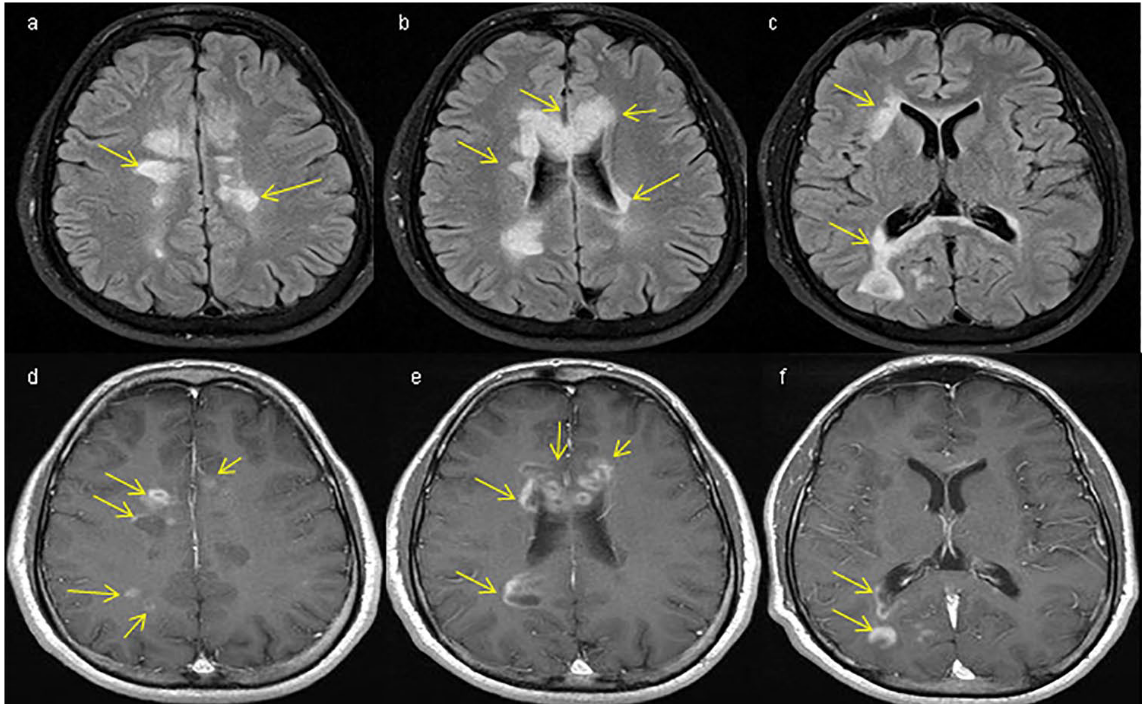

Vírus John Cunningham (JCV)

NATALIZUMABE

LEMP

- 2008 Foi descrito o primeiro caso de LEMP

- 2010-2011 Identificado o tempo de uso da droga e o uso prévio de imunossupressores como fatores de risco

- 2011-2012 Presença do anticorpo Anti-JCV como fator de risco

- 2016-2017 Avaliação do risco mensurada pelo Índice JCV

- 2014-2016 Monitorização por exames de RM mais frequentes

Risco de LEMP monitorizado pelo Índice JCV

Risco de LEMP, Índice JCV e Frequencia de Imagem

- Pacientes com risco de LEMP se beneficiaram da realização mais frequente de RM a cada 3-4 meses

- Foi possivel identificar o aumento de volume, identificar melhor as características e a disseminação